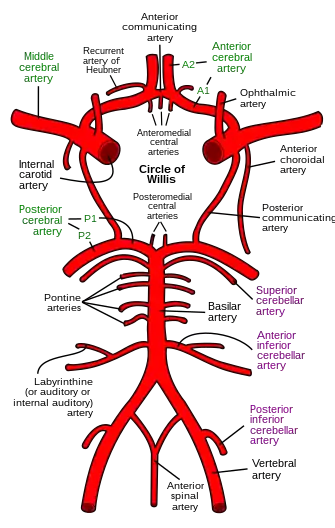

The internal carotid arteries supply oxygenated blood to the front of the brain and the vertebral arteries supply blood to the back of the brain.[55] These two circulations join in the circle of Willis, a ring of connected arteries that lies in the interpeduncular cistern between the midbrain and pons.[56]

The internal carotid arteries are branches of the common carotid arteries. They enter the cranium through the carotid canal, travel through the cavernous sinus and enter the subarachnoid space.[57] They then enter the circle of Willis, with two branches, the anterior cerebral arteries emerging. These branches travel forward and then upward along the longitudinal fissure, and supply the front and midline parts of the brain.[58] One or more small anterior communicating arteries join the two anterior cerebral arteries shortly after they emerge as branches.[58] The internal carotid arteries continue forward as the middle cerebral arteries. They travel sideways along the sphenoid bone of the eye socket, then upwards through the insula cortex, where final branches arise. The middle cerebral arteries send branches along their length.[57]

The vertebral arteries emerge as branches of the left and right subclavian arteries. They travel upward through transverse foramina which are spaces in the cervical vertebrae. Each side enters the cranial cavity through the foramen magnum along the corresponding side of the medulla.[57] They give off one of the three cerebellar branches. The vertebral arteries join in front of the middle part of the medulla to form the larger basilar artery, which sends multiple branches to supply the medulla and pons, and the two other anterior and superior cerebellar branches.[59] Finally, the basilar artery divides into two posterior cerebral arteries. These travel outwards, around the superior cerebellar peduncles, and along the top of the cerebellar tentorium, where it sends branches to supply the temporal and occipital lobes.[59] Each posterior cerebral artery sends a small posterior communicating artery to join with the internal carotid arteries.